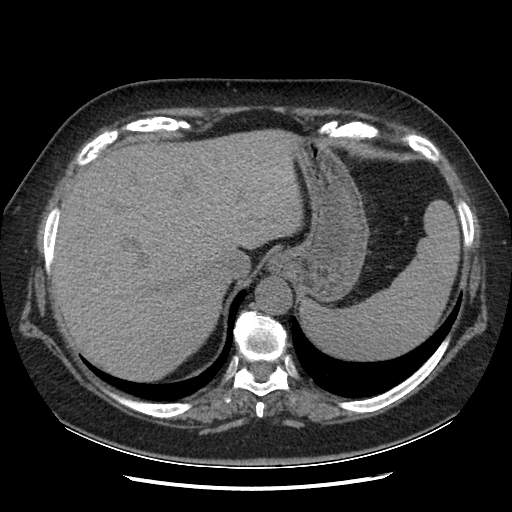

Generated VENOUS CT scan (A→B translation)

Lung window (WL -600, WW 1500 β†’ Low βˆ’1350, High +150)